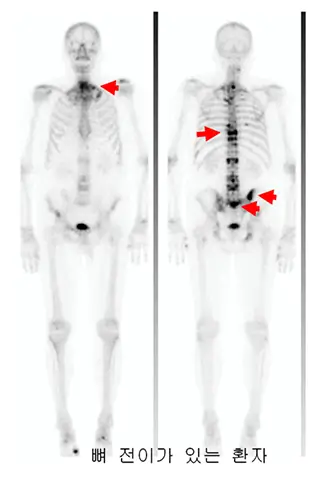

뼈스캔

- 폐암이 뼈로 전이되었는지 확인하기 위해 시행되며, 방사성 동위원소를 주입하여 뼈에 축적되는 방사선을 감지해 전이 여부를 진단합니다. 뼈 전이는 폐암 환자에게서 흔히 발생하며, 이를 조기에 발견하는 것이 중요합니다.